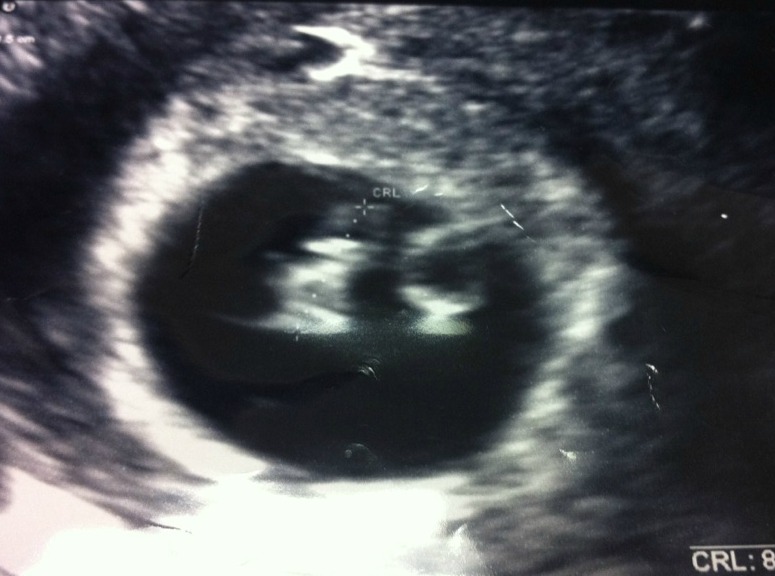

Yup. That there’s a baby, unofficially known as Tater. Okay, so it’s actually a uterus holding a baby, which is the thing on the left. Well, we’ve been told it’s a baby. I’m holding out for a pony. Tater was only six weeks along right there, which is why she looks like a seahorse. Which is almost like a pony, but not.

So yeah. I am pregnant. Preggers. Knocked up. Bun in the oven. My eggo is preggo. I am WITH CHILD. (I hate that one, it creeps me out…) Due July 24th, but that’s up in the air because I was three weeks early and my husband was three weeks late and ain’t been on time since.